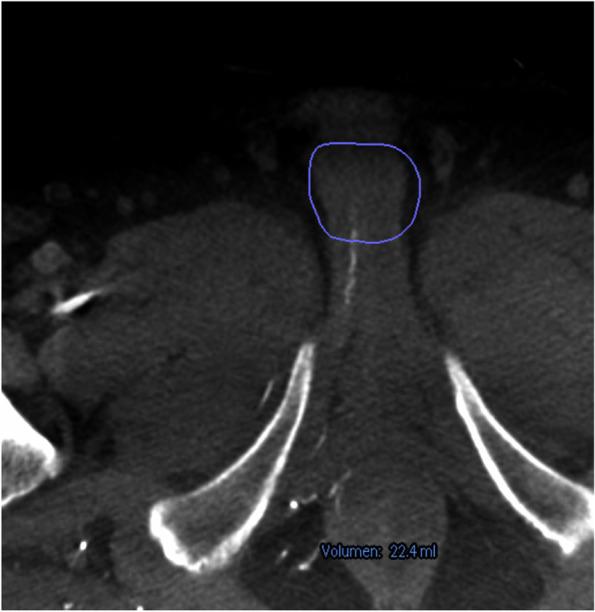

TECHNIQUE

We report a novel technique of using C-arm Cone-Beam CT and vessel navigation software to facilitate super-selective catheterization.

我们报告了一种使用C形臂锥形束CT和血管导航软件来促进超选择性导管插入术的新技术。